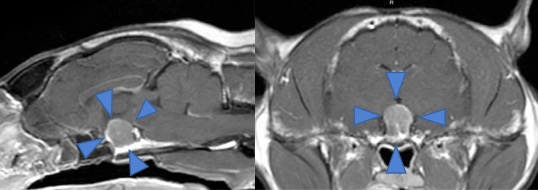

MRI画像所見/下垂体腫瘍

MRIでは下垂体が非常に大きくなっており(矢印で囲った部分)、直上にある間脳、中脳(脳幹の一部)を圧迫していました。

通常の下垂体は約2~3mm程度ですが、この症例では9mm程度まで大きくなっていました。大きくなった下垂体により正常な脳が圧迫され、意識障害やふらつきが生じている状態と考えられました。